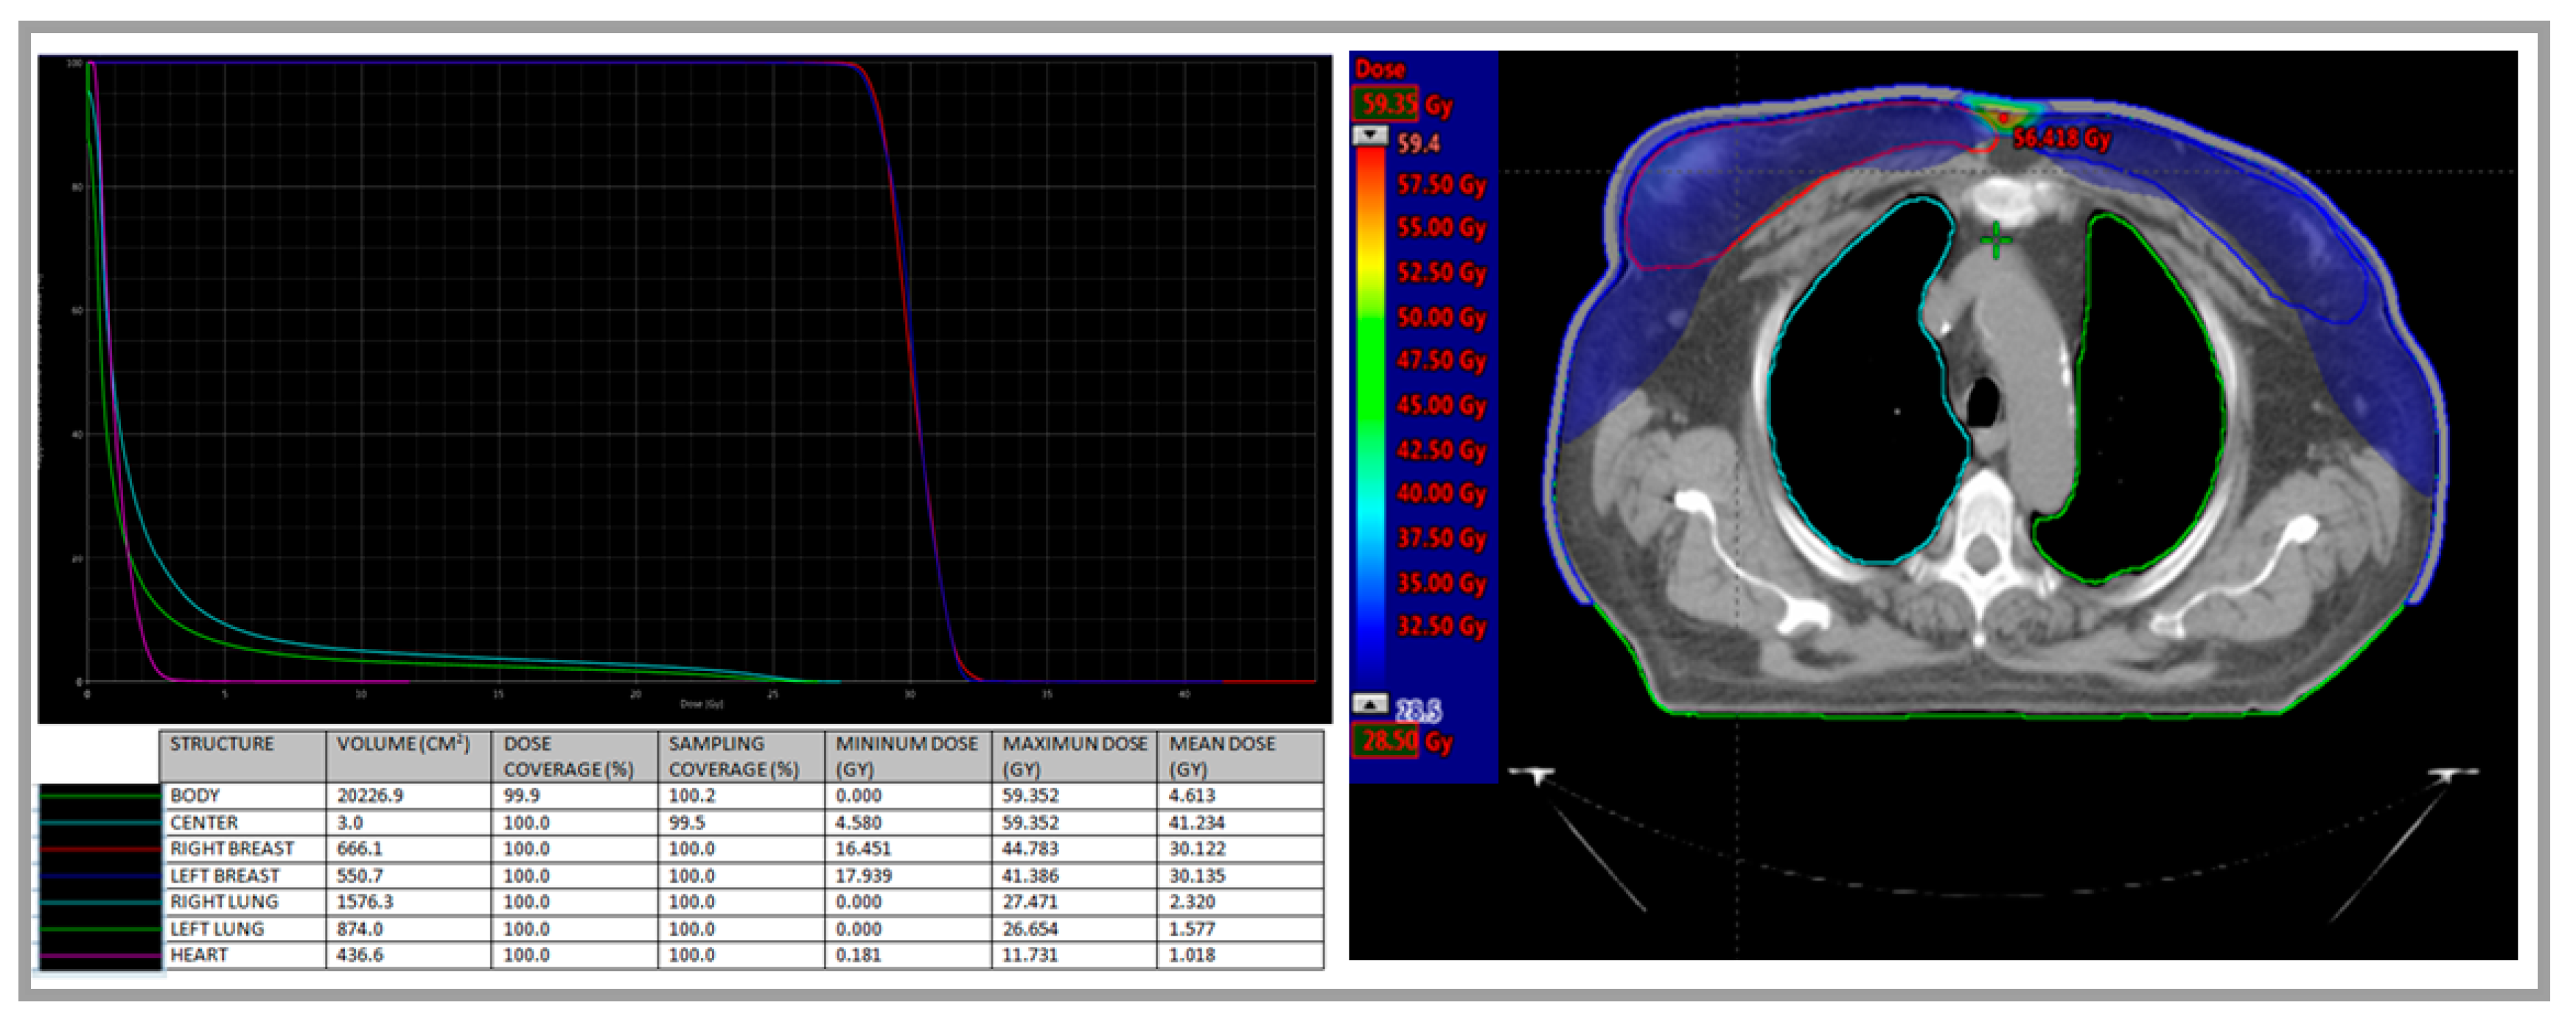

2. Case Presentation